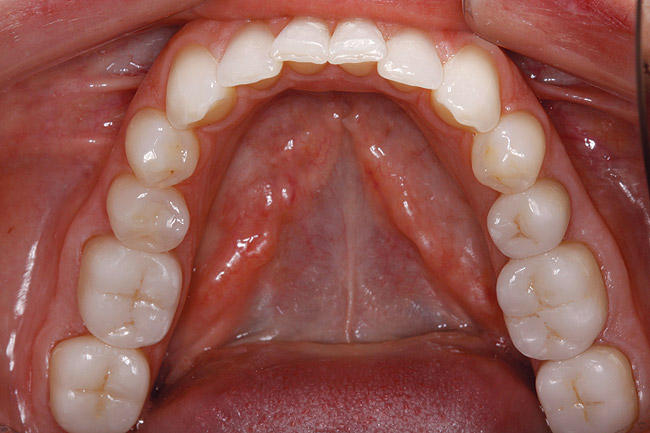

A female patient presented seeking improved esthetics and full-mouth reconstruction for her smile for personal and professional reasons. A dynamic and vibrant personality with a high-profile career in the dental industry, she wanted a smile that was equally impactful. Clinically, she presented with an extensive amount of dentistry that had been done on an as-needed basis. She was conscious of the different optics resulting from the various materials used, and their contrasting appearance with one another as well as with adjacent natural teeth. Bilateral disharmonies and different clinical crown heights were evident (Figure 1).

Figure 1  A magnified 1:2 view of the patient’s smile shows bilateral disharmonies as the patient smiles with medium lip dynamics.

Figure 1